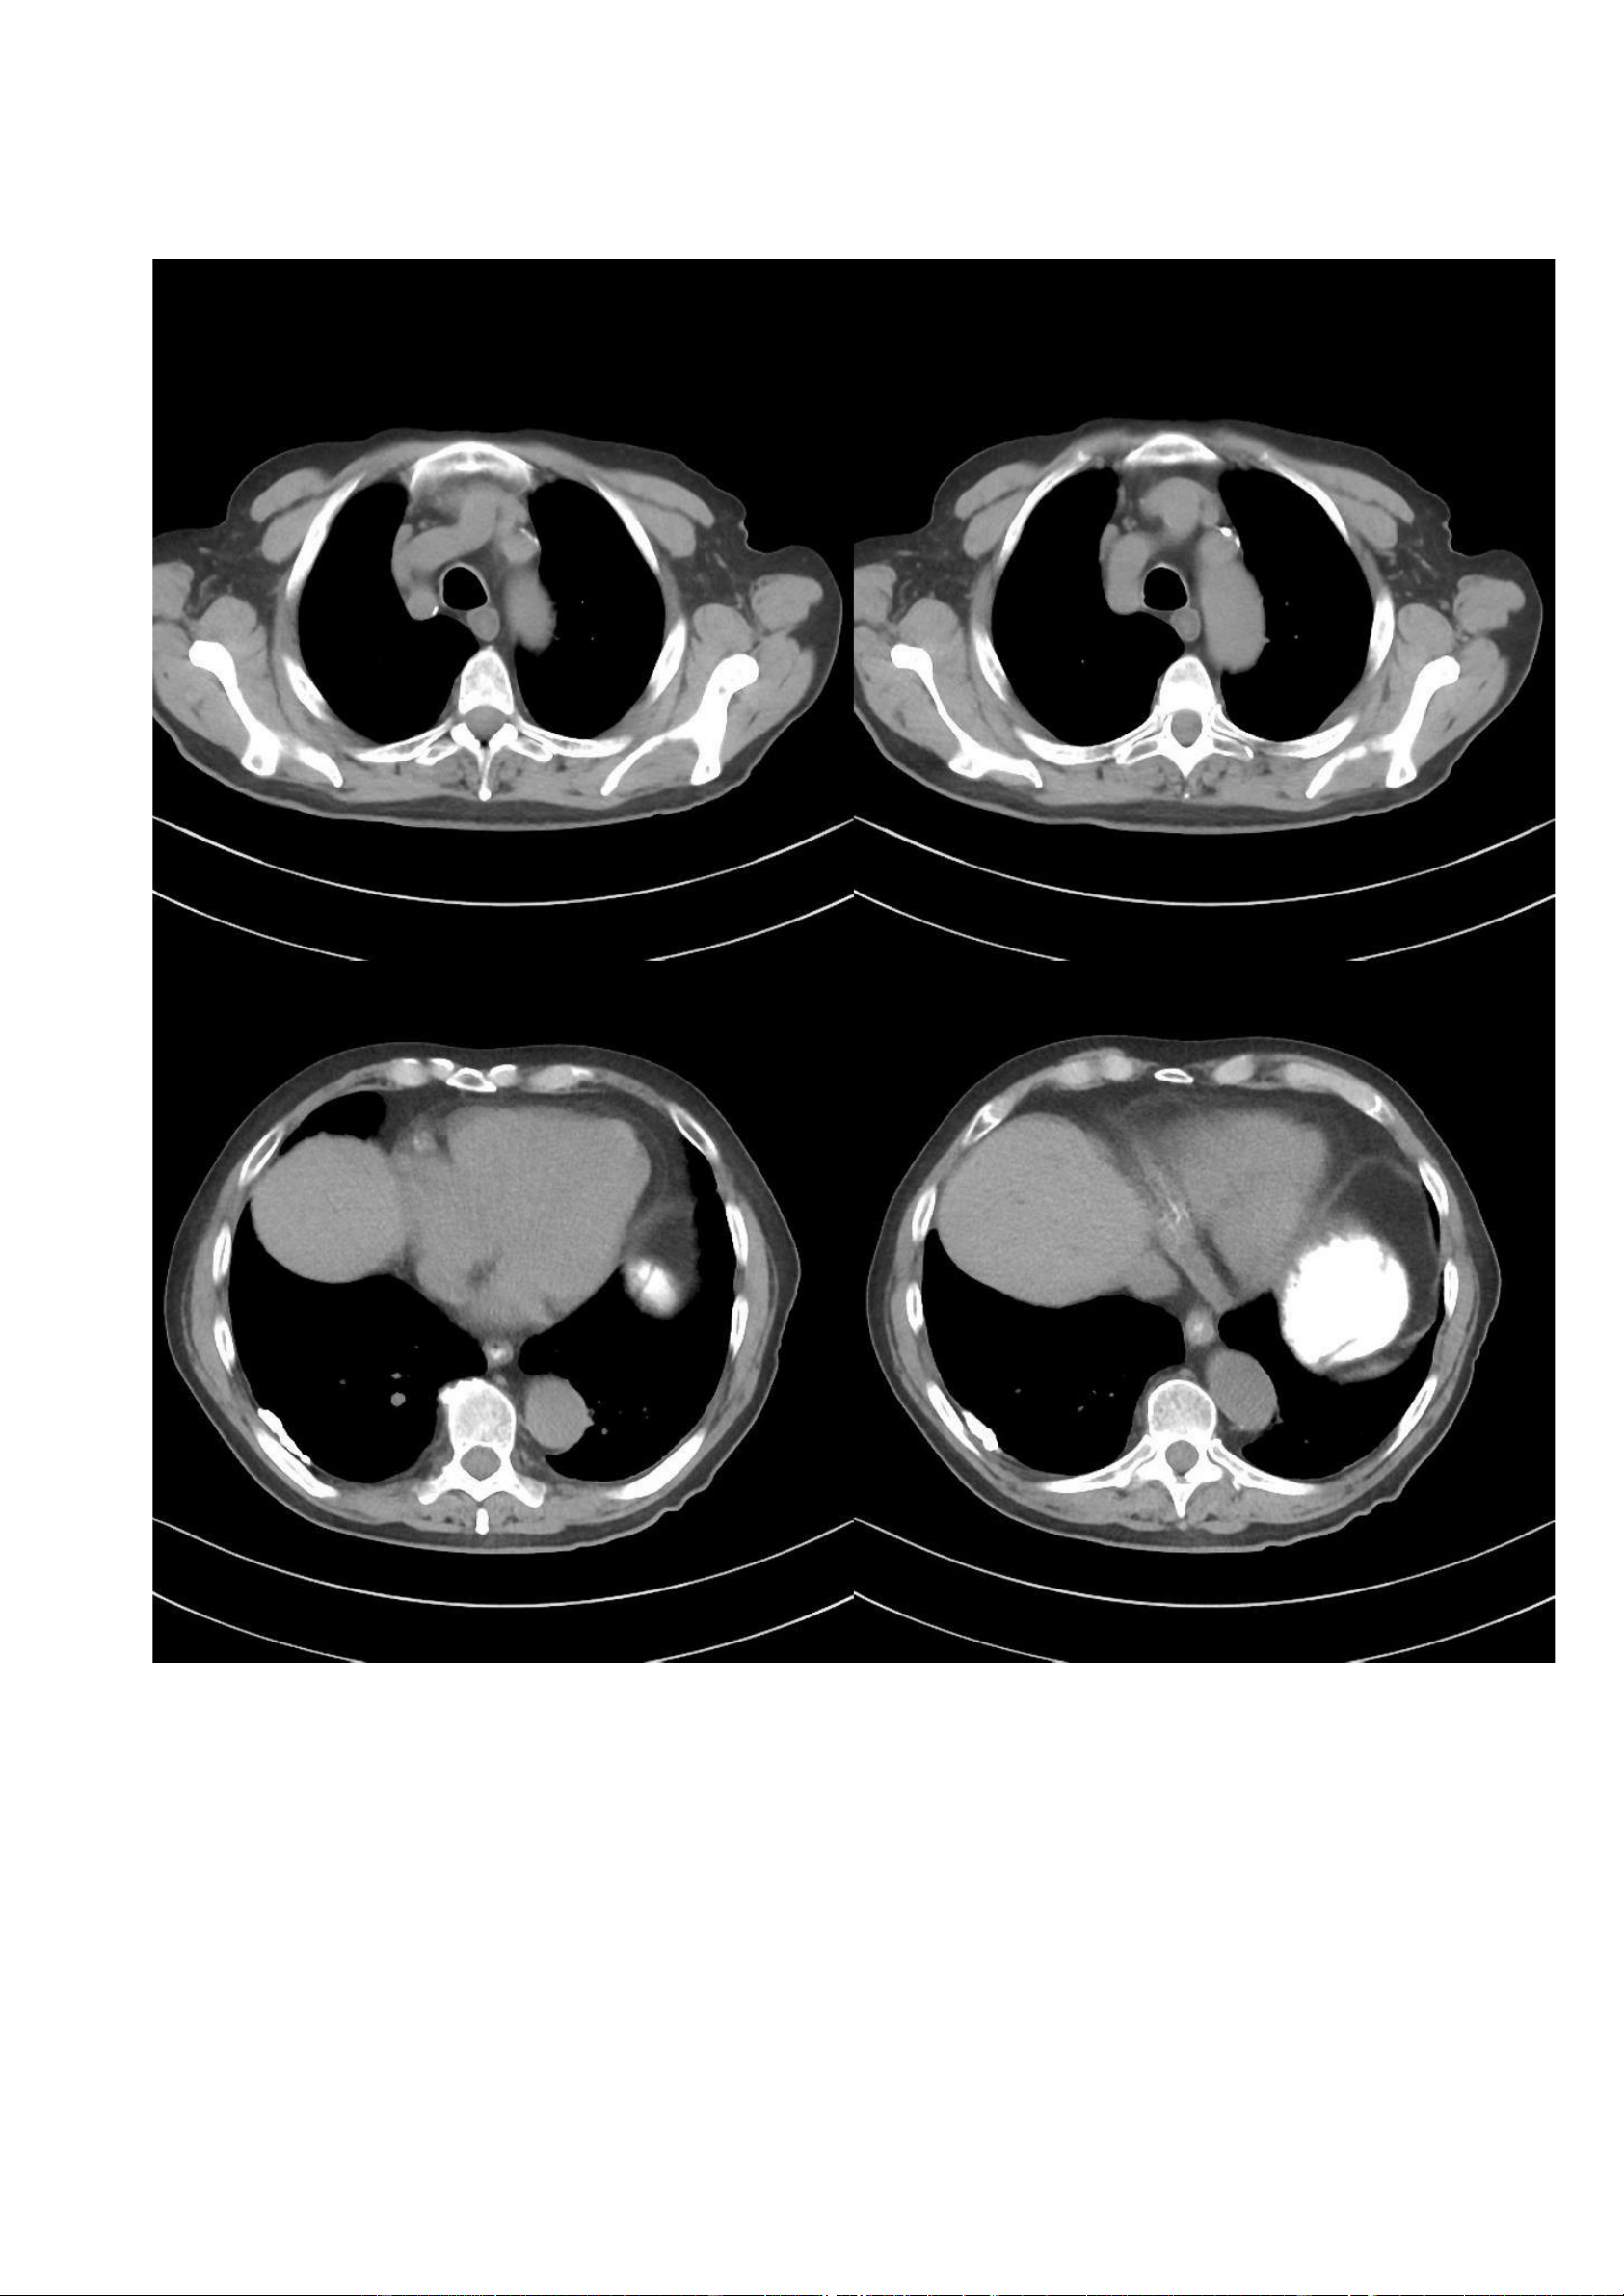

Hình ảnh CT (cửa sổ xương): lOMoAR cPSD| 22014077 Phan Tùng Bách

Các hình ảnh CT được lựa chọn cho thấy sự hiện diện của các màng màng phổi vôi hoá, đặc biệt là ở phần

trước-ngoài của màng phổi thành. Một vài mảng màng phổi không vôi hoá ở phần sau. Màng phổi trung thất và

các góc sườn hoành bình thường. 7.2. Trường hợp 2: -